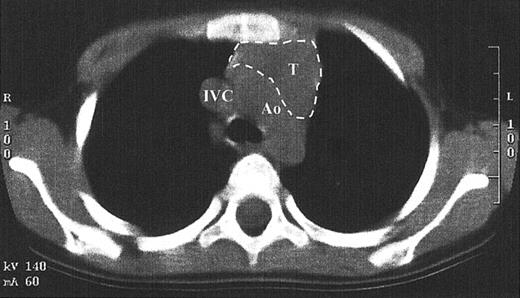

While TRECs are an excellent surrogate marker for thymic function, little direct data exist that show thymopoiesis. This is in part due to the inappropriateness of performing a thymic biopsy in children who have developed normal function. Since the pretransplantation SCID thymus is vestigial, weighing less than a gram, it is difficult to find by radiography.1,14 A computed tomography scan of the anterior mediastinum of the Jak3-deficient SCID patient at 4 years after transplantation shown in Figure 6demonstrates a thymus with a transverse dimension of 3.8 cm, which is normal for age.16 The thymus expansion seen here provides further evidence for thymopoiesis after hematopoietic stem cell transplantation in SCID.

Computed tomography scan of the anterior mediastinum of a Jak3-deficient SCID patient 4 years after transplantation.

Thymic tissue is indicated by the dashed lines. It is in the normal position and measures 3.8 cm in its greatest transverse dimension, which is normal for age. Ao indicates aortic arch; IVC, inferior vena cava; T, thymus.

In addition to having a higher survival rate, SCID patients receiving transplants in the neonatal period demonstrated increased lymphocyte proliferation to PHA and higher numbers of CD3+ and CD45RA+ T cells when compared with those receiving transplants after the first 28 days of life. Superior T-cell reconstitution was most evident from 3 months to 3 years after transplantation. This is a critical period for the development and maturation of host defenses in response to new pathogens that are frequently encountered at a young age. The observed differences in T-cell function can be attributed to higher thymic output after transplantation in the SCID neonates than in the older SCID infants. This conclusion is supported by the finding of higher TREC levels, higher numbers of circulating CD3+ T cells, higher numbers of CD45RA+(naive) T cells, and more vigorous early T-cell proliferation to mitogens in the neonates than in the older group. This supposition is also confirmed by the finding of a normal-sized thymus at 4 years after transplantation in one patient in whom computerized tomography of the thymus was obtained. In aggregate, these findings confirm our previous conclusion that the vestigial SCID thymus is able to support T-cell development from donor stem cells.14 One explanation for a favorable effect of early stem cell transplantation for SCID may be that those SCID infants receiving transplants after the neonatal period may have already suffered from recurrent or opportunistic infections, malnutrition, and failure to thrive. Stress from these comorbid factors could have had a deleterious effect on thymic function.